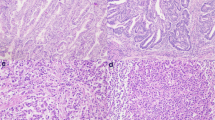

Representative images of LGR5 and CD8 in MMR-P and MMR-D cases. Representative features in MMR-D (a) and MMR-P (d). In MMR-D, many CD8-positive lymphocytes were observed (b) and LGR5 expression was low (c). In MMR-P, few CD8-positive lymphocytes were observed (e) and LGR5 expression was high (f). (a and d, HE; b and e, CD8 immunostaining; c and f, LGR5 RNAscope)

LGR5 RNA expression in PD-CRC with MMR protein deficiency

We evaluated LGR5 expression in all PD-CRC cases. All 29 cases contained carcinoma cells with some LGR5-positive dots, with a wide range of LGR5-positive cell staining. Representative images of LGR5 staining in MMR-D and MMR-P cases are shown in Fig. 2c and f. LGR5 H-scores varied among the cases. Mean H-scores for LGR5 staining in MMR-P and MMR-D cases were 62.9 (24.2–136.2) and 24.4 (7.9–63.4), respectively. LGR5 H-scores in MMR-D cases were significantly lower than those in MMR-P cases (P = 0.034) (Fig. 3).